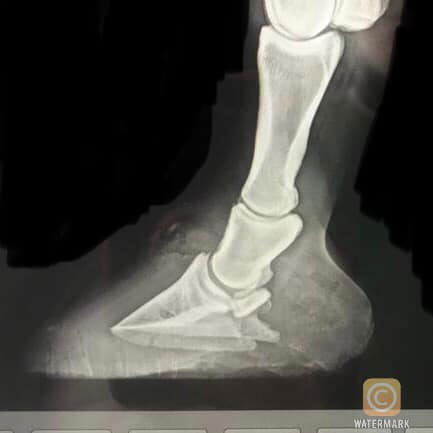

“This emergency case came to me with laminitis/ imbalance of the hooves.

I worked to create hoof balance using the support of Glushu with padding.